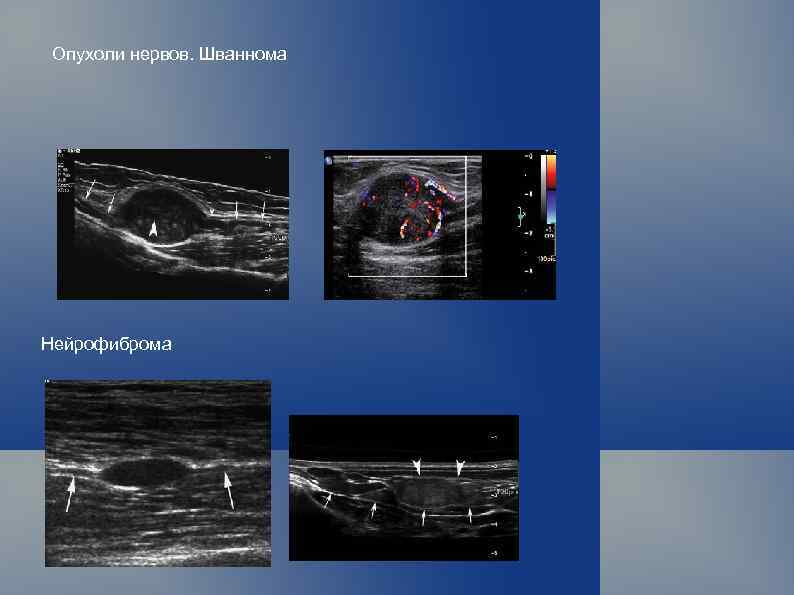

Классификация опухолей мягких тканей (ВОЗ, 1969 г. ) Опухоли мезотелиальной ткани. Доброкачественная мезотелиома. Злокачественная мезотелиома. Опухоли и опухолевидные поражения периферических нервов. Доброкачественные: травматическая неврома; невро-фиброма; неврилемома (шваннома); неврофиброматоз (болезнь Реклингаузена). Злокачественные: злокачественная шваннома (неврогенная саркома, неврофибросаркома);

Опухоли нервов. Шваннома Нейрофиброма

Гранулярно-клеточная опухоль нерва